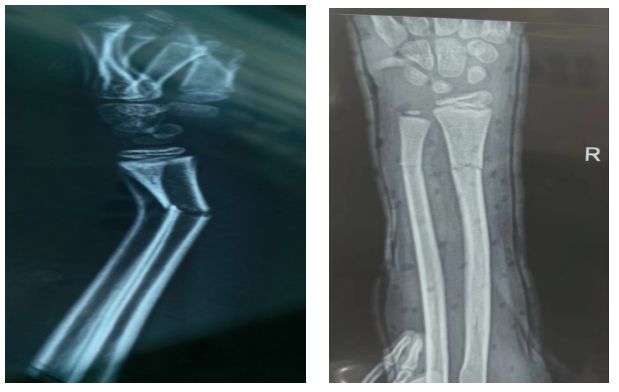

一名患者家属

今年八月的一天晚上,叮铃铃,我的电话铃响起,是我家小侄女在玩耍中不小心右臂错位,在当地医院拍片后,医生告诉家属要去上一级医院就诊,如果当地医术高超,孩子不用手术可以复位,否则需要钢板植入。家人抱着忐忑的心情来到急诊外科,正好是王鑫主任值班,他沉着冷静三下五除二就搞定了,拍片对照复位成功,家属怀着激动的心情万分感激。